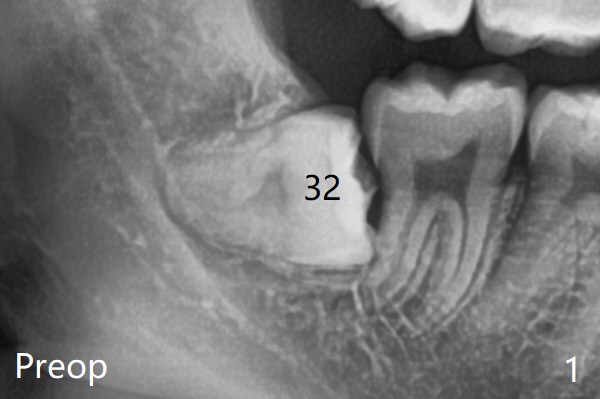

A 22-year-old man, asymptomatic, is going to have #1,16,17 and 32 extracted (Fig.1, fully bony impaction). For the large lower sockets (actually Buccal Impaction), collagen plug is placed in the inferior half, while Bone Cement (Bond Apatite from Augma (Fig.3 A)) and Osteogen plug (O) in the superior half at #32 and 17, respectively.